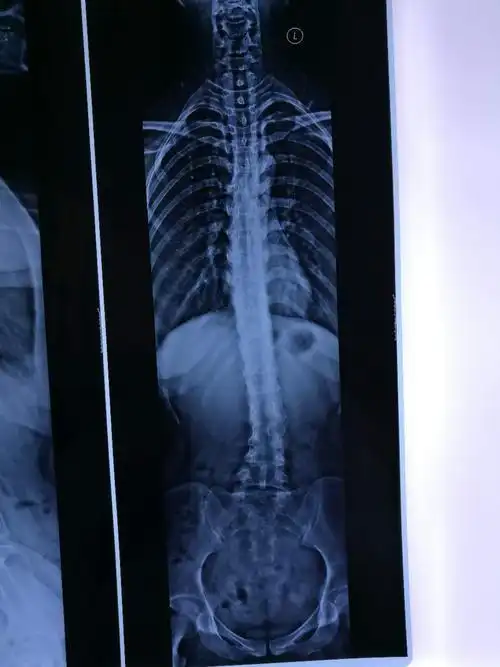

下腰椎侧弯

先天腰间盘突出,脊柱达到45度弯曲的人有多痛苦?

25岁女性,腰椎变弯情况已经有1-2年了,现在直不起腰来,有疼痛感,请